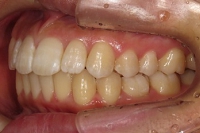

CASE3

前歯1本だけが出ています、矯正で治りますか?

(23歳/女性)↓

||||||||

概要・担当医コメント:

前歯の唇側傾斜/マルチブラケット装置/非抜歯

動的治療期間15ヶ月(15回)/費用概算:60万円.

歯列アーチの形態修正に必要なスペースを微量のエナメル質の研磨により創生し,当初の計画通りに歯を移動させました.